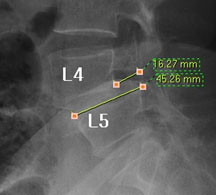

즉, 척추전방위증은 통증을 일으키는 원인질환(디스크, 협착증)을 치료하는 것이 척추 뼈를 더 이상 앞으로 밀려나가지 않게 하는 치료라고 볼 수 있습니다. 모커리는 뼈가 50% 이상 밀려나간 2단계의 척추전방위증도 비수술로 치료하고 있으며, 이러한 한방치료 효과를 객관적으로 검증하여 유명학회 및 논문에 계속해서 발표하고 있습니다.

모커리한방병원은 50% 정도 밀려나간 2단계의 척추전방위증 환자를 대상으로 약 3주간의 입원집중치료를 실시한 결과, 입원 시보다 80% 이상 통증이 감소되어 치료되었습니다. 통증 없이 걷는 시간도 약 3배 정도 증가되어 단기간에 수술 없이 높은 치료효과가 나타났다는 것을 대한침구의학회에 발표하였습니다. 50% 정도 밀려나간 2단계의 중증 척추전방전위증 환자이면서 심한 척추협착증 증상을 나타내는 환자를 치료한 결과입니다.